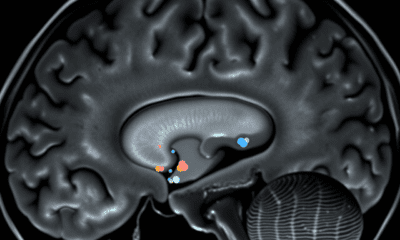

A new study challenges a decades-old assumption in neuroscience by showing that the brain uses distinct transmission sites -- not a shared site -- to achieve...